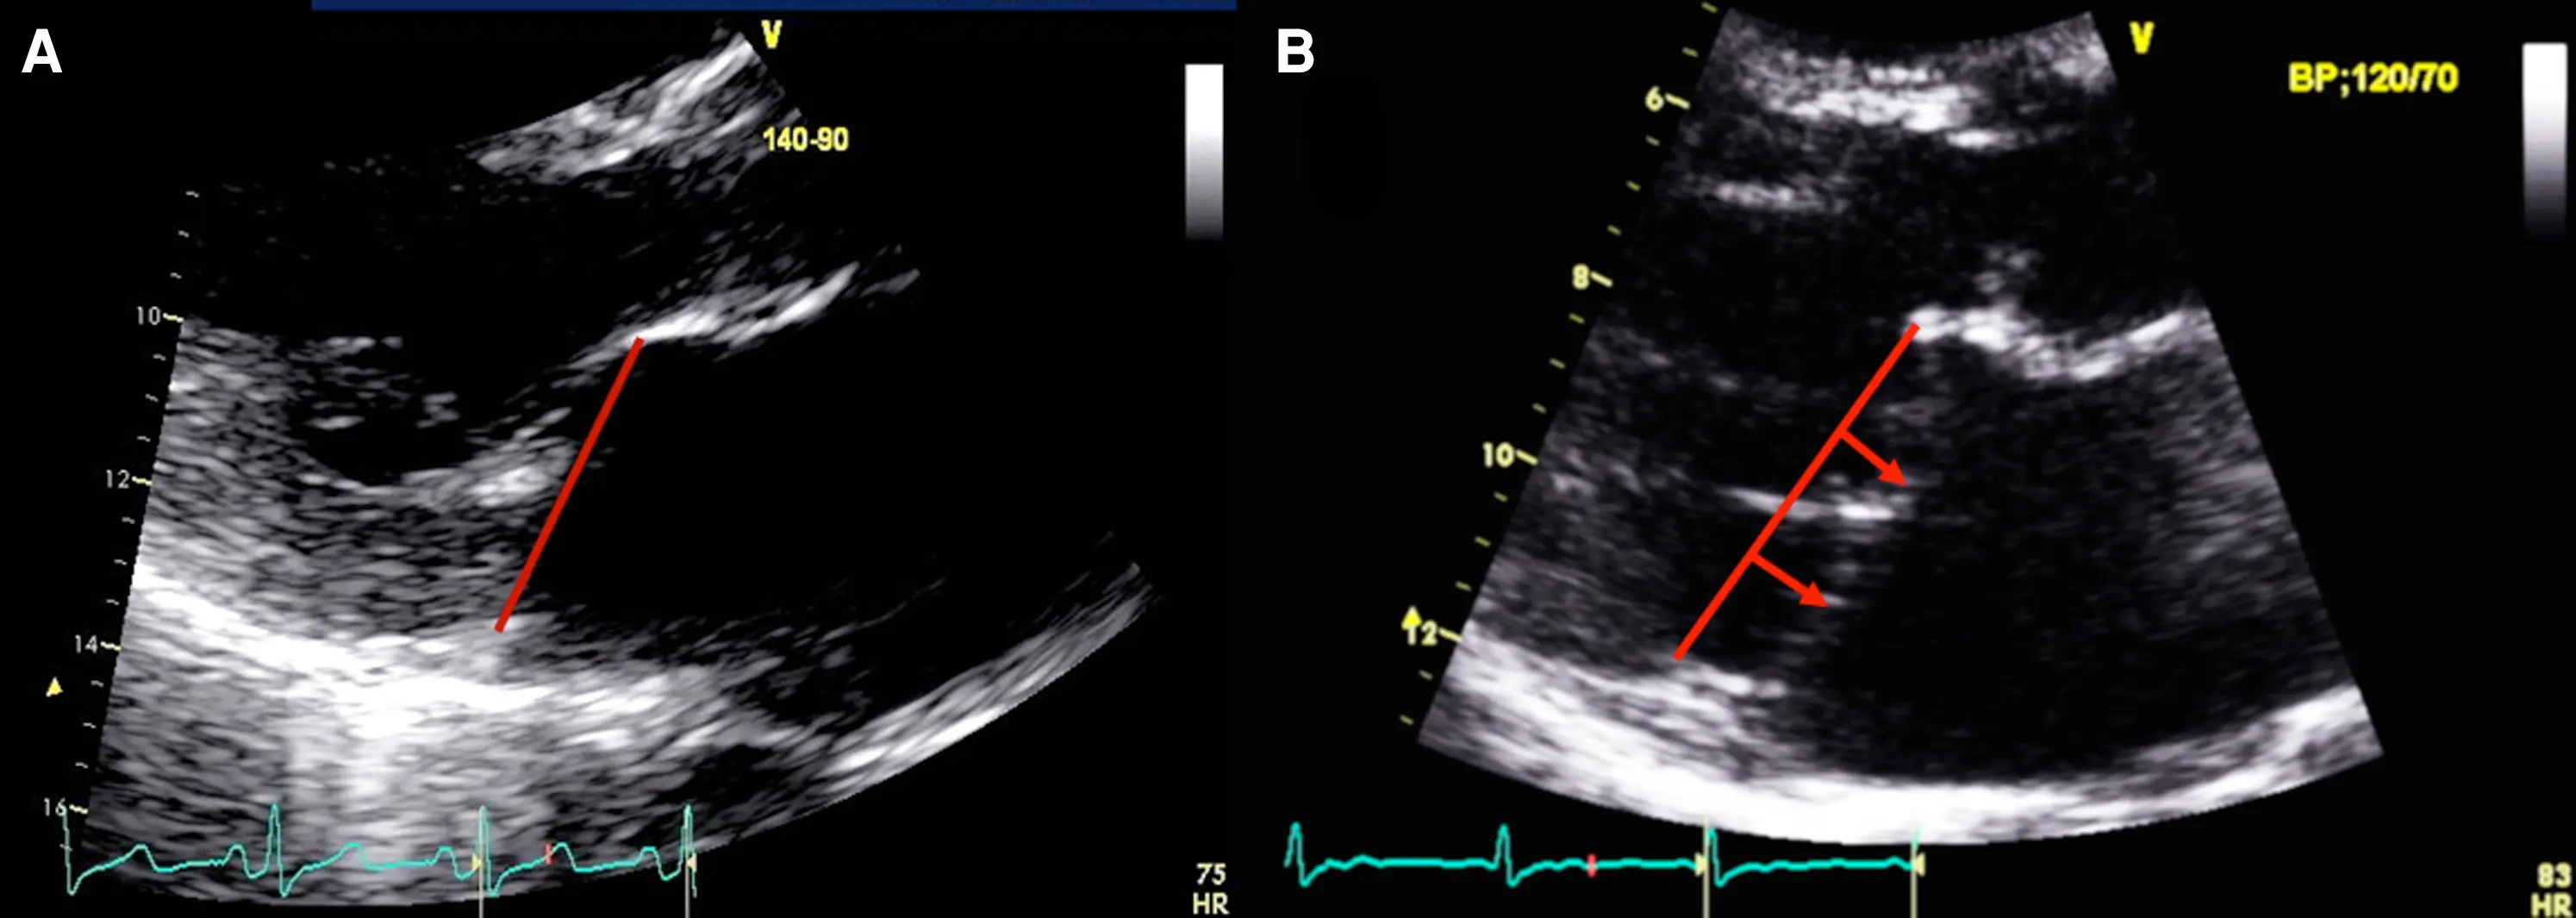

Echo

- Using echocardiography, MVP is diagnosed ideally in the PLAX window as systolic displacement of the mitral leaflet into the LA of ≥2 mm from the mitral annular plane.

- If parasternal windows are of poor quality, the apical long-axis view can also be used, although the latter is less standardized and thus more variable.

- ⛔ Diagnosis of MVP should be avoided in the A4C or A2C windows

- Structural abnormalities that increased risk of A-MVP syndrome include increasing degrees of myxomatous degeneration of valve leaflets, leaflet redundancy, bi-leaflet prolapse, and the presence of mitral annular disjunction (MAD)